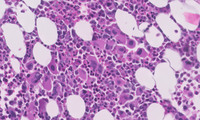

Figure 2: Images of bone marrow core biopsy in CML–accelerated phase

Low power image demonstrating markedly hypercellular marrow with significantly increased numbers of megakaryocytes visualized at higher power.  The image at the bottom depicts numerous megakaryocytes that comprise an admixture of dwarf forms with hypolobated nuclei (typical in CML) as well as forms comprising micromegakaryocytes with dysplastic features.  The background comprised and equal admixture of maturing myeloid and erythroid precursors without the typical myelocyte bulge seen in chronic myeloid leukemia, chronic phase.